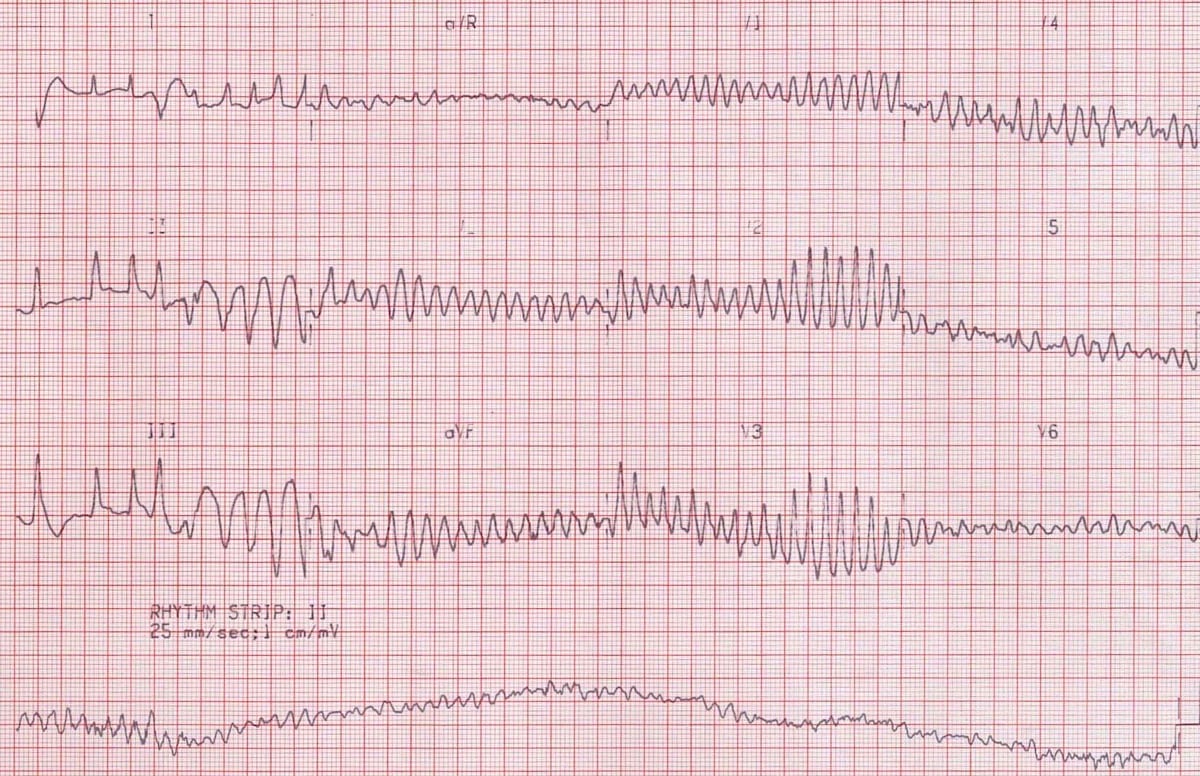

This is an ECG of monomorphic VT. Note the very regular, broad complex tachycardia and the same QRS morphology throughout.

https://litfl.com/ventricular-tachycardia-ecg-library/

© Life in the Fast Lane. Licensed under CC BY-NC 4.0

This is an ECG of polymorphic VT (specifically, Torsades de Pointes – a type of polymorphic VT). The varying QRS morphology can be appreciated, with the characteristic morphology of QRS complexes “twisting” around the isoelectric line.

https://litfl.com/torsades-de-pointes-ecg-library/

© Life in the Fast Lane. Licensed under CC BY-NC 4.0

This is an ECG of VF. Note that it looks very chaotic, and no waveforms or patterns can be identified.

https://litfl.com/ventricular-fibrillation-ecg-library/

© Life in the Fast Lane. Licensed under CC BY-NC 4.0